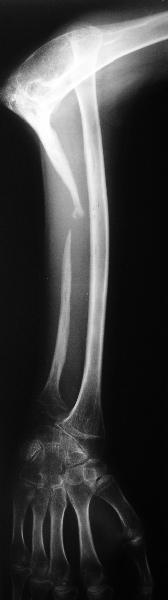

Молодой человек 2-3 года назад наблюдался по поводу прогрессирующего остеолиза правой локтевой кости. Морфологически - гемангиома, возможно, ангиомоподобный остеолиз (болезнь Gorham-Stout). Получал лучевую терапию. К настоящему времени остеолиз не прогрессирует. Однако сформировался вывих лучевой кости. Рентгенограмма и функция - см. иллюстрации. Пациенту хотелось бы улучшить функцию. Что можно предложить? Постепенное вправление аппаратом, замещение дефекта локтевой кости, резекцию головки лучевой, оставить как есть, что-то еще?

Судя по рентгенограмме, сформировался плечелоктевой артродез под углом около 90 градусов, поэтому тот объем движений, который выполняет пациент, обеспечивается за счет дефекта локтевой кости.